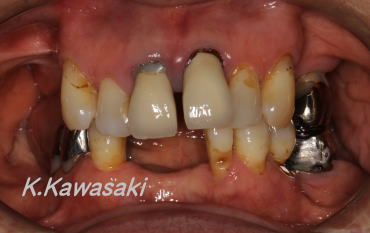

| 歯の無い部分と見た目の改善を希望して来院されました。上下奥歯、下の前歯が歯周病でありませんでした。上の前歯もグラグラでした。 |

奥歯が無くなると、残った歯に慢性的に負担がかかり、歯は様々な場所に移動してしまいます。インプラント、ブリッジなどの治療の際、本来の位置に歯を戻してあげることがとても重要です。移動には部分矯正治療が有効です。 |

| 奥歯と下の前歯にはインプラント、上の前歯にはブリッジを装着し機能性・審美性を回復させました。ところで上の前歯はどこが無いかおわかりでしょうか? |

真ん中2本がありません。しかし事前に精密な処置を施すことで、まるで本当に歯が生えているかのように再現することが可能です。 |